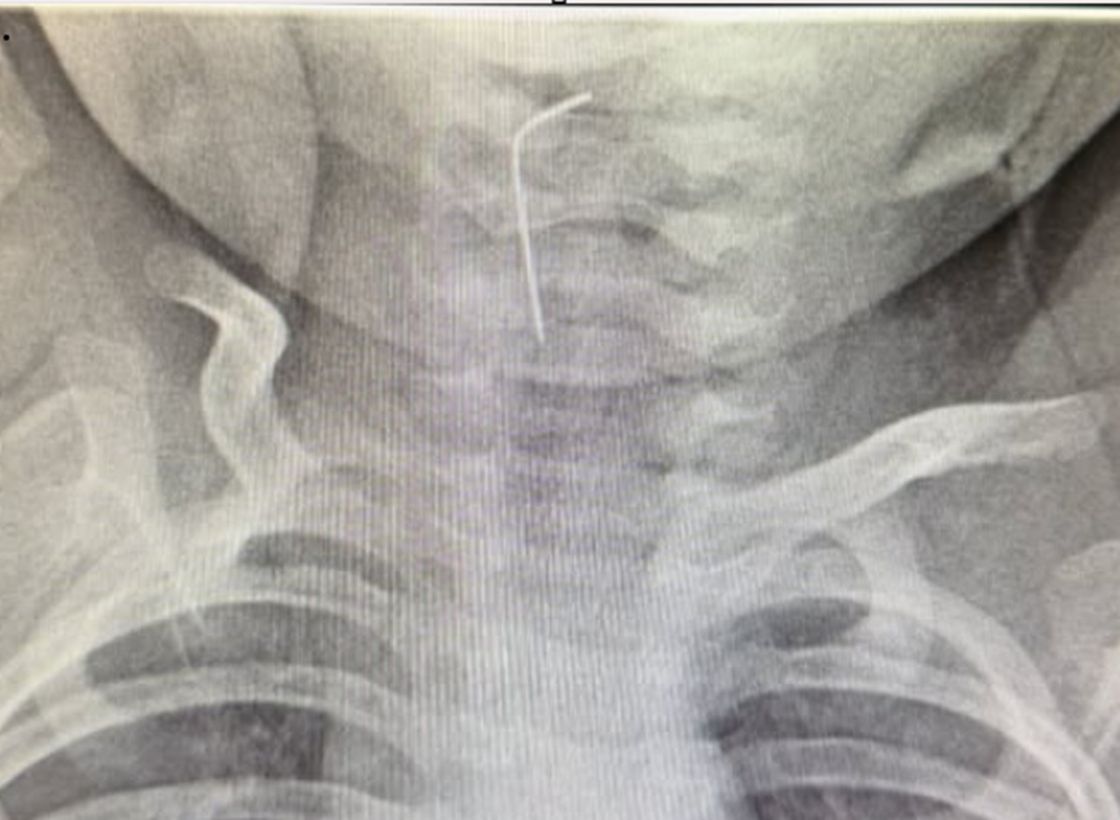

Анықталғандай, сәби абайсызда ине жұтып қойған. Дәрігерлер дереу рентгенологиялық тексеру жүргізіп, бөгде заттың нақты орналасқан орнын анықтаған.

Түркістан облыстық балалар ауруханасының мамандары – хирург Мұқағали Темірбеков пен эндоскопист Бабыр Ырысқұлов өңеште тұрып қалған бөгде затты сәтті алып шыққан.

Алынған ине

Алынған ине. Фото: instagram.com/turkistandsb

"Уақыт жоғалтпай, эндоскопиялық әдіс қолданылып, өңеште тұрып қалған ине сәтті түрде алынды. Медициналық көмектің жедел әрі кәсіби көрсетілуінің арқасында ықтимал асқынулардың алдын алу мүмкін болды", - делінген хабарламада.